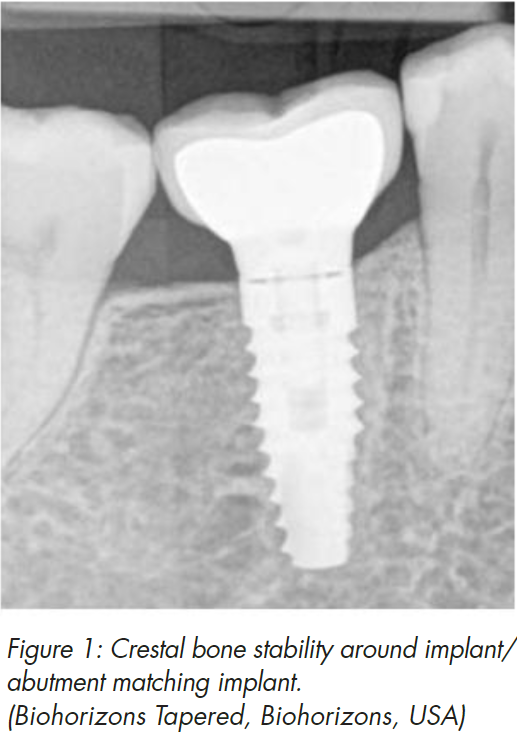

Crestal bone stability around dental implants remains one of the most important and wanted features of successful implant treatment. Besides major clinical advantages to the patient, stable marginal bone provides us, the clinicians, with psychological comfort and satisfaction, because of positive long-term outcome (Fig 1). Therefore we all need to be aware of possible causes, which can lead to loss of crestal bone stability and exercise every method to prevent bone resorption.